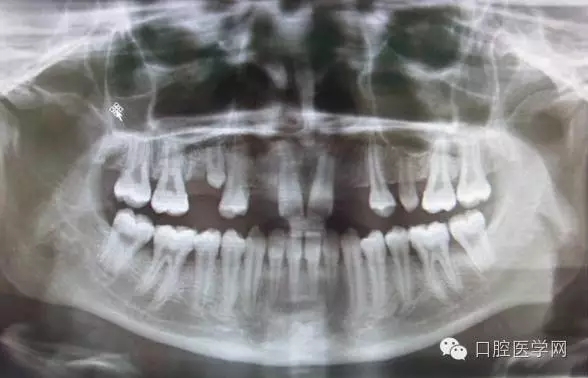

3.牙齒數(shù)目異常

額外牙

X線表現(xiàn):最多見于上頜兩中切牙之間;圓錐形,根短小;拍攝X線片可確定額外牙的數(shù)目、位置、形態(tài)與鄰牙的關(guān)系。

先天缺牙

X線表現(xiàn):常為對稱性;確定缺牙數(shù)目。